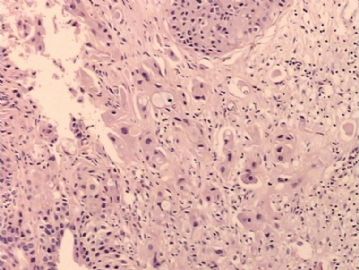

腺鳞癌?

姓    名: ××× 性别:   年龄:  39岁

标本名称:  宫颈活检

简要病史:  同房出血3次,tct HSIL

考虑:原位腺癌,小灶性区域有鳞状上皮向间质内浸润,考虑有鳞状细胞癌结构。